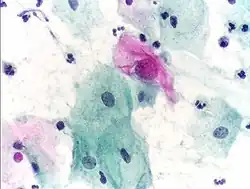

Micrograph of a Pap test showing a low-grade intraepithelial lesion (LSIL) and benign endocervical mucosa. Pap stain. -

Pap tests commonly examine epithelial abnormalities, such as metaplasia, dysplasia, or borderline changes, all of which may be indicative of CIN. Nuclei will stain dark blue, squamous cells will stain green and keratinised cells will stain pink/ orange. Koilocytes may be observed where there is some dyskaryosis (of epithelium). The nucleus in koilocytes is typically irregular, indicating possible cause for concern; requiring further confirmatory screens and tests.